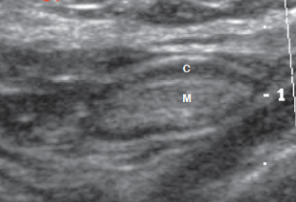

Normal lymph node US appearance

• < 1cm AP diameter

• Shape: oval (long axis), C-shaped (short-axis)

• Hypoechoic cortex

• Hyperechoic fatty hilum

• Uniform vascular hilum